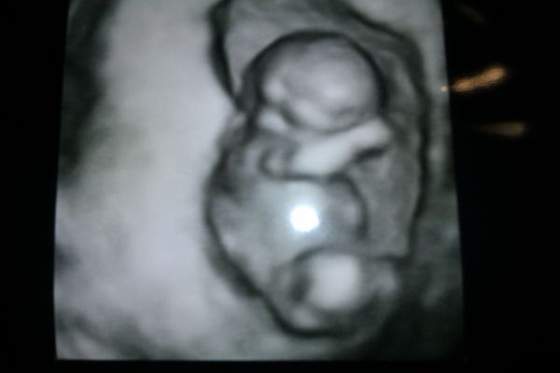

lekarz widząc moją minę na samą myśl o tym ( dużo się naslucham od dziewczyn, że to ohyda) powiedział " Spokojnie proszę mi zaufać " ciekawe czy sam próbował